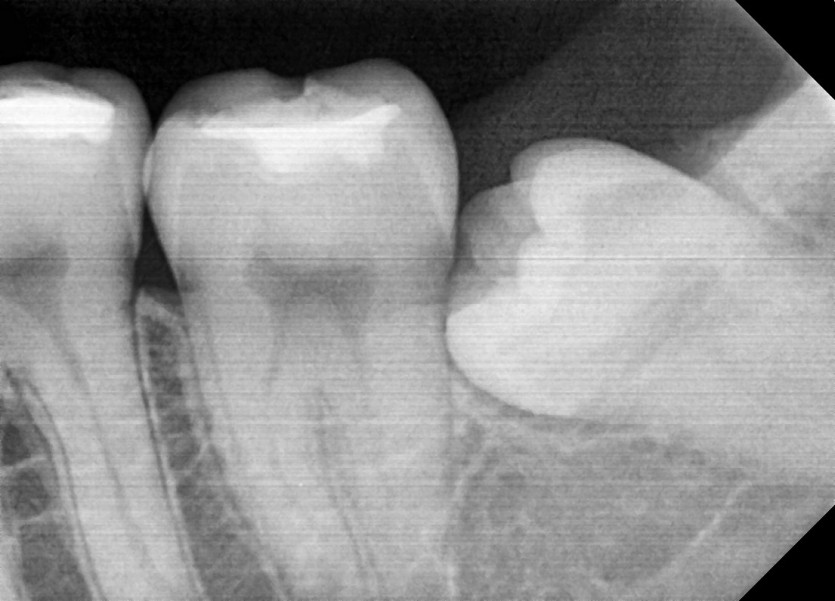

#28,38 사랑니 발치

구강 외과 전문의가 당일 발치하였습니다.